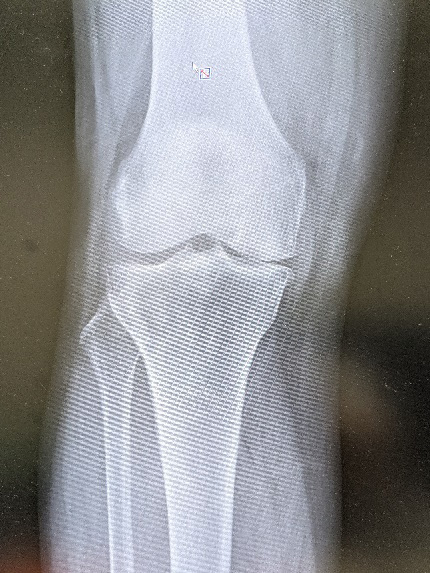

脛骨近位骨切り術

骨切り術は、膝の骨の角度を調整し、関節の負担を分散し痛みの軽減を図る手術です。通常関節鏡視下での半月板手術と併用されることが多く、自身の関節を温存できるため、スポーツや仕事で膝をよく使う方やどうしても人工関節に抵抗がある活動性の高い方に適しています。基本的に術後1年程度で抜釘します。

内側開大脛骨近位骨切り術軽度のO脚変形に対し行われます。

逆V脛骨近位骨切り術高度のO脚変形に対し行われます。